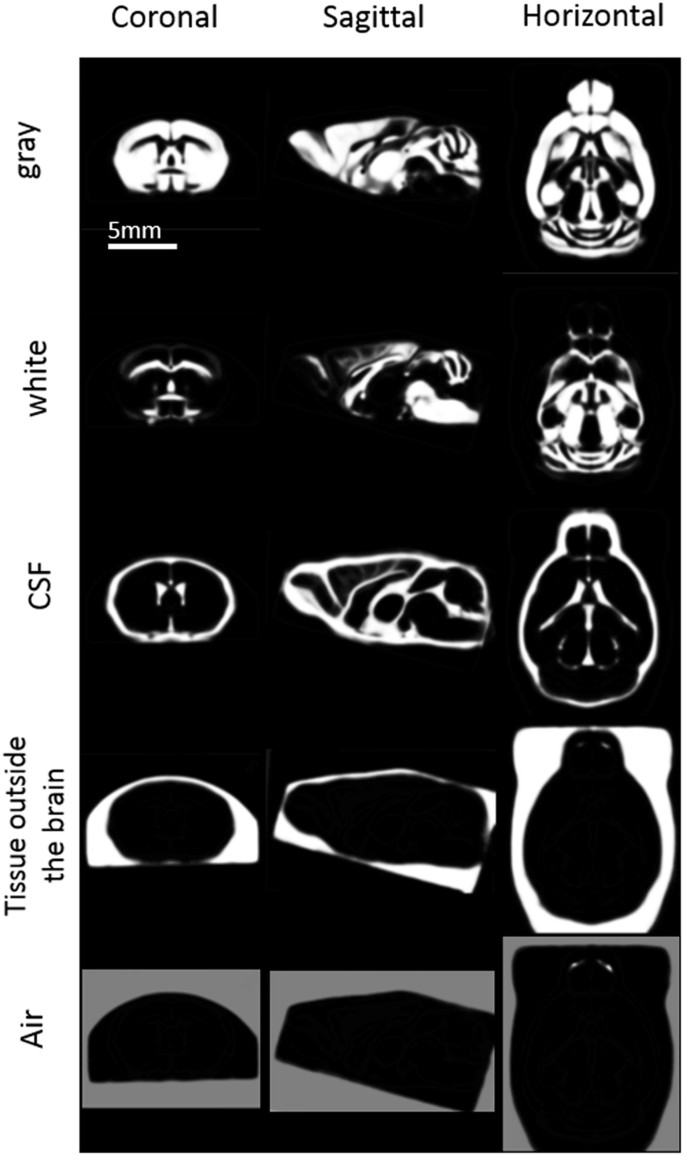

A two-stage process was used to segment the head images into gray matter (GM), white matter (WM), cerebrospinal fluid (CSF), tissue outside the brain, and air, as follows. First, the “Segmentation” tool in SPM8 was used for all skull-stripped mouse brain data. The data were divided into GM, WM, and CSF images using a mixture of Gaussians and tissue probability maps (TPMs) of the SPM Mouse. An in vivo brain template was then created by using the DARTEL toolbox (Ashburner, 2007) in SPM8, which improves registration with an inverse consistent, diffeomorphic transformation. Next, the in vivo brain template was employed to average each set of data for tissue outside the brain and air as probability maps for segmentation, respectively. DARTEL in SPM8 was also used to finally complete an in vivo brain template, including tissue outside the brain and air.

The bounding box (a three-dimensional (3D) space) encompassed the following x, y, and z dimensions and the origin in mm: x = −6.8, 6.8; y = −9.8, 7.4; z = −8.7, 2.2; and origin = 0, 0, 0. The horizontal slice (z = 0) passed through the height of the Bregma, while the coronal slice (y = 0) lay perpendicular to the horizontal plane and passed through the Bregma. The sagittal slice (x = 0) was located at the median sagittal plane. The stereotaxic, population-averaged, tissue-segmented brain templates created from the C57Bl/6, BALB/cBy, C3H/H3, and DBA/2 mice have been made freely available (http://www.nitrc.org/projects/tpm_mouse).

Based on the in vivo microscopic T1WIs for the C57Bl/6, BALB/cBy, C3H/He, and DBA/2 mouse brains, we created a population-averaged standard brain template for each strain (Fig. 1), including TPMs (C57Bl/6 in Fig. 2). All of these templates are freely available (http://www.nitrc.org/projects/tpm_mouse). The differences between coordinates in selected landmarks of the template and a photomicrographic atlas by Franklin & Paxinos19 are shown in Table 1; there was a relatively small average difference of 0.09 mm in the x direction, 0.02 mm in the y direction and 0.08 mm in the z direction.